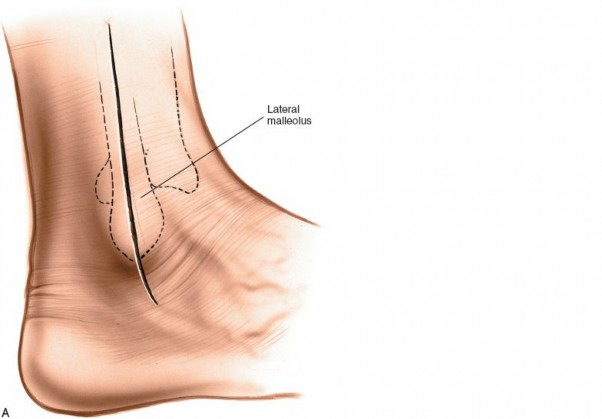

- Padding: Minimal padding is used to ensure "total contact." Felt pads are placed over the malleoli, the tibial crest, and the navicular prominence. Foam padding is placed over the toes to protect them from the hard cast shell.

- Positioning: The ankle must be held in neutral (90 degrees) during application to prevent equinus contracture, which would paradoxically increase forefoot pressures.